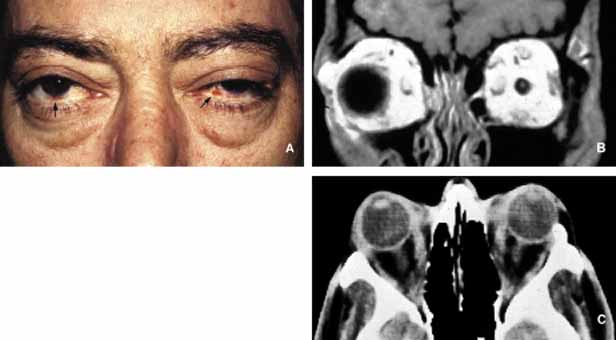

Many metastatic neoplasms originating from other organ systems may find their way to the orbit by hematogenous spread. The most common metastatic malignancies include breast, lung and kidney carcinomas, cutaneous melanoma and rarely sarcomas originating elsewhere in the body.160–162 Tumor-like conditions such as pseudotumors, granulomas, congenital lesions (hamartomas, choriostomas, etc.) that may also invade orbit secondarily are covered elsewhere in this chapter. Both the clinician who evaluates the patient with an orbital space occupying lesion and the pathologist who examines the tissue removed from an orbital mass, must have a working knowledge of the frequency of orbital neoplasms and tumor-like conditions163–166 (Table 4). More commonly encountered acquired orbital neoplasms are detailed. PRIMARY TUMORS Epithelial Neoplasms Primary epithelial neoplasms of the orbit originate from the ductal and acinar epithelium of the lacrimal gland.167,168 The most commonly encountered lacrimal gland tumor is pleomorphic adenoma (benign mixed tumor) (BMT). This neoplasm is known as a “mixed” tumor because it is composed of a mixture of epithelial and stromal elements (Fig. 14). The epithelial elements of the tumor consist of glandular and ductal formations that may develop squamous metaplasia and small keratin filled cysts. The stroma is composed of myxoid tissue that may contain cartilage and bone. In most cases the BMT of the lacrimal gland is multilobulated and surrounded by a fibrous capsule. If additional smaller lobules are present in the vicinity of the main lesion, these satellite nodules are individually encapsulated as well. When malignancy develops within a BMT it is classified according to its predominant histopathologic component as adenocarcinoma within pleomorphic adenoma, adenoid cystic carcinoma, or poorly differentiated carcinoma. Malignant transformation may happen as a rapid growth within an unknown tumor or may take place decades after diagnosis of the BMT.169 Adenoid cystic carcinoma, the most common malignant tumor of the lacrimal gland may also develop de novo. This is a highly malignant neoplasm that can be seen in adolescents and may develop rapid extension into the adjacent structures including the cranium by direct invasion and to the base of the skull by painful perineural invasion.170,171 The histopathologic appearance of adenoid cystic carcinoma may present as several variants including the most common “Swiss cheese” pattern that consists of cribriform clustering of small basophilic tumor cells surounded by thick basement membrane (Fig. 15). Other types including diffuse basaloid, sclerosing, tubular, and comedocarcinoma are known to exist.172 Both benign and malignant tumors of the lacrimal gland present with proptosis and inferior medial displacement of the globe that can readily be demonstrated on CT and MRI studies showing cavitation of the lacrimal fossa in chronic benign lesions and direct invasion of the bony tissues in malignant tumors. Adenocarcinoma developing in BMT (pleomorphic adenocarcinoma, malignant mixed tumor) presents with atypical features within tubular and glandular structures.169 Mucoepidermoid carcinoma of the lacrimal gland consists of diffuse proliferation of atypical squamous cells with abundant vacuolated cytoplasm containing mucin. The clinical course of mucoepidermoid carcinoma is chronic with a relatively favorable prognosis.173,174 Other than true neoplasms, cystic dilatation of the lacrimal gland ductules that is known as dacryops and ectopic lacrimal gland tissue presenting in areas away from the anatomic site of the gland also present as space occupying lesions in the lacrimal fossa.175–177 Mesenchymal Neoplasms The traditional grouping of the primary vascular tumors in the orbit include capillary and cavernous hemangiomas, lymphangioma and arteriovenous malformations. The current thinking is that these lesions represent hamartomas that are made of different tissue components and may be better defined as “vascular hamartomatous lesions.”178 Histopathologic examination of these tumors often reveals mixtures of above listed tissue elements, the symptomatology, clinical course and response to treatment depends on the predominating histopathology. For example, if capillary hemangioma is the dominating element of a vascular tumor it is most often apparent at birth or within the first year, occurs in the anterior orbit and gradually regresses without any treatment. 179 Approximately 70% of capillary hemangiomas regress completely by 7 years of age. Patients with orbital capillary hemangioma may also have similar lesions in other organs. If systemic involvement is extensive, secondary thrombocytopenia known as Kasabach-Merritt syndrome develops. These lesions grossly appear as bright red, strawberry-like masses; histopathologically they are made of sheets of vascular endothelial cells with small lumen formations. Basement membranes surrounding these cells can be clearly identified with a reticulin stain. The predominating cell of the lesion is confirmed to be endothelial cell, by the positive staining for factor VIII, CD31 and CD34. The identification of an intracytoplasmic organelle known as Wiebel-Palade body by transmission electron microscopy also confirms the nature of the tumor cell as vascular endothelium (Fig. 16). For adnexal and orbital capillary hemangioma the treatment options include observation, intralesional and systemic corticosteroids, systemic interferon and in some cases surgical excision and radiation therapy.180–182 Another type of orbital tumor that originates from blood vessels is hemangiopericytoma, which is a pseudoencapsulated spindle cell tumor composed of vascular pericytes183 (Fig. 17). In these tumors the reticulin network surround the individual tumor cells in hemangiopericytoma as opposed to small groups of epithelial cells in capillary hemangioma. In hemangiopericytoma the tumor cells stain positively with factor VIII, CD34, and occasionally vimentin. The histopathologic pattern that may present considerable pleomorphism with increased number of mitotic figures may vary from one zone to the other. The degree of pleomorphism and high number of mitotic figures are not clear cut indications of malignancy; as a matter of fact, the biological behavior of this tumor cannot be determined based on its histopathologic appearance. Metastatases after many years have been described.184 The best treatment for hemangiopericytoma is surgical excision. Cavernous hemangioma is another benign vascular tumor that occurs in adults, usually as a solitary, unilateral lesion, but multiple tumors have been described.185,186 Unlike capillary hemangioma it is not associated with other lesions elsewhere in the body. It is usually located within the muscle cone but may also be seen in extraconal locations and presents with slowly progressive proptosis without too much extraocular motility disturbance (Fig. 18). Gross appearance of cavernous hemangioma is a well encapsulated reddish purple lesion with a sponge-like consistency on its cut surface. Histopathologically, it consists of dilated vascular channels lined by endothelium and smooth muscle and intervening fibrous stroma. The endothelial cells are held together by tight junctions and display basement membrane reduction. Clinical differential diagnosis of cavernous hemangioma on imaging include fibrous histiocytoma, hemangiopericytoma, schwannoma and metastatic tumors.187 Surgical removal of the tumor is the treatment of choice. Another lesion of this category that presents with large cavern formations surrounded by different amounts of fibrous tissue is lymphangioma.188–190 Unlike cavernous hemangioma, however, the space formations in this lesion are not lined by endothelial cells and do not contain vascular smooth muscle; the spaces are lined by flat mesothelial-like cells (Fig. 19). Spontaneous bleeding may take place within these cystic spaces resulting in “chocolate” cysts. In one-third of the cases, lymphoid follicles with germinal centers may be present in the intervening fibrous stroma and some tumors with abundant lymphoid tissue may respond to systemic steroid treatment. Because of the infiltrating nature of this tumor, surgery is not an early option of management; these lesions should be managed conservatively.190 Orbital varix is another orbital vascular lesion that develops as a distention of a venous channel leading to stagnant blood flow resulting in thrombus formation.191 Orbital varices are divided into primary lesions, confined to the orbit and secondary lesions associated with intraorbital and intracranial arteriovenous malformations.54 Vascular hamartomatous lesions may contain arteriovenous malformations with or without abnormal communication between arterial and venous vasculature. These lesions should not be confused with carotid cavernous and dural cavernous fistulas, which affect the orbit secondarily.192 If one clinically suspects an A-V malformation component in an orbital vascular lesion, CT angiogram and arterial and venous angiograms should be used to rule out the connection of the lesion to systemic circulation.193 Color Doppler flow imaging has also been used to examine these tumors. In addition to the above detailed vascular tumors, angiosarcoma, Kaposi sarcoma, intravascular papillary endothelial hyperplasia (IPEH), vascular leiomyoma and angiolymphoid hyperplasia with eosinophilia (Kimura disease), can rarely be encountered in the orbit.194–198 In this chapter, neural neoplasms are covered under two major groups: tumors originating from central nervous system (CNS) tissues, and tumors originating from peripheral nerves. The two most commonly encountered tumors of the optic nerve that involve the orbit are optic nerve glioma and optic nerve meningioma.200 Optic nerve glioma (ONG) is primarily a tumor of childhood.201,202 When it presents in adults a more malignant glioma should be suspected.203 ONG is associated with neurofibromatosis type I (NF-I) with one or both optic nerves involved in approximately 25% of the cases.204 Some authors suggest that patients with NF-I may have a favorable prognosis. In general, the more anterior the glioma, the more favorable the prognosis.205 These tumors produce painless progressive visual loss and proptosis and ophthalmoplegia.206 Optic disc swelling and atrophy is generally present and rarely optociliary shunt vessels may develop.207 Neurofibromatosis (NF) is subdivided into types I and II. It is an autosomal dominant multisystem disease characterized by multiple tumors and developmental abnormalities.208,209 Neurofibromatosis type I presents with numerous ocular adnexal and orbital manifestations including optic nerve and chiasm gliomas and optic nerve sheath meningioma (Fig. 20). Histopathologically ONG is a low-grade pilocytic astrocytoma.210,211 The tumor is composed of proliferating fibrillary astrocytes that may show different degrees of pleomorphism and vascular proliferation (Fig. 21). The axonal component of the nerve is not involved with the neoplastic process during the early stages of the disease. Mitotic figures and necrosis are associated with malignant transformation into higher grades. These tumors show pleomorphic cellular changes, with increased mitotic rate and necrosis. Long standing ONG (”ancient” glioma) may develop degenerative changes including dilated processes of glial cells (Rosenthal fibers) and hyalinization.200 The diagnosis of these tumors has significantly improved with the advances of neural imaging, particularly with MRI and the role of biopsy in the management ONG has become more or less obsolete.212 In unusual cases in which there is rapid tumor enlargement accompanied by visual loss, biopsy may reveal useful information to differentiate between ONG and meningioma and may help in documenting the presence of a malignant glioma. Interpretation of the biopsy sample may be difficult because of the infiltration of the subarachnoid space with pilocytic astrocytes that are similar in appearance to meningeal fibroblasts.213 Another pitfall that should be remembered is that the arachnoidal hyperplasia secondary to ONG may be misinterpreted as a primary meningioma.214 The treatment of ONG includes surgical excision if the extension into the cranium is imminent. Radiation and chemotherapy are generally reserved for patients older than age 5 years with worsening of signs and symptoms.215 Meningioma is a slow-growing tumor originating from the meningoendothelial cells of the arachnoidal layer of the optic nerve or the cranial meninges. These tumors may occur primarily in the optic nerve sheath or extend into the orbit secondarily from the cranial cavity.200 The symptoms of optic nerve meningioma (ONM), which typically affects white, middle-aged females, include slowly progressive, painless loss of vision and proptosis. As the disease progresses, there may be disc edema, orbital ciliary shunts, and optic atrophy.216 Histopathologically meningioma shows varying patterns of meningoendothelial proliferation including sheets of polygonal cells, mixed proliferation of elongated meningoendothelial cells with fibroblasts, and the psammomatous type in which the meningoendothelial cells form eddies to surround calcified psammoma bodies (Fig. 22). Immunohistochemically, they are positive for EMA and vimentin (Fig. 22). Two other types of more aggressive histopathologic patterns are known: the angioblastic and sarcomatous. These lesions have a tendency to recur and extend into adjacent bone and occasionally metastasize. Although a malignant behavior is not predictable in all cases, high mitotic rate implies worse prognosis; cell cycle markers such as MIB-1 may be useful in evaluation of borderline aggressive cases. There is an increased incidence of bilateral and multiple meningiomas in neurofibromatosis I and II.217 ONM is usually diagnosed with ultrasonography, CT and MRI.218 Therefore, biopsy is only needed in atypical cases. Surgical treatment of ONM leads to total loss of vision; therefore, it is saved as a last resort for eyes without vision or for unusually large lesions with potential extension into the cranium. Currently radiation therapy is the treatment of choice from the standpoint of long-term preservation of the vision.219,220 Peripheral nerve tumors of the orbit originate from the ciliary ganglion and from cranial nerves III, IV, V, and VI, which are ensheathed by Schwann cells. Schwannoma (neurolemoma) is a benign tumor that originates from the Schwann cell.221 This adulthood tumor accounts for approximately 1% of all orbital tumors 222 Most cases are solitary and unilateral and have a predilection to the superior orbit originating from the branches of supraorbital or supratrochlear nerves.221–223 Approximately 25% of schwannomas demonstrate enlargement of the superior orbital fissure and invasion of the cavernous sinus on CT and/or MRI.224 Schwannoma generally occurs as an isolated tumor; however, in approximately 10% of cases it is associated with neurofibromatosis.225 Histopathologically this encapsulated tumor is composed of proliferation of Schwann cells that in areas reproduce the pattern of the nerve sheath. The cells that have indistinct cellular borders and oval nuclei form either solid structures (Antoni A pattern) or a loose arrangment in a background of finely granular eosinophilic material (Antoni B pattern) (Fig. 23). Isolated clusters of tumor cells (Verocay bodies) are diagnostic.221,226 Older tumors show degenerative changes with increased areas of myxoid differentiation, collagenation and necrosis. These changes are seen in long-standing tumors that are known as “ancient” schwannomas and on MRI present with a cavitary appearance that can be confused with a cystic orbital tumor.227 Very rarely the schwannoma demonstrates increased cellularity of spindle-shaped cells with pleomorphic nuclei and hyperchromatism.228 The malignant tumor usually presents with a plexiform pattern of irregularly swollen nerve bundles containing spindle-shaped cells. Malignant transformation of schwannoma is very rare but once this occurs the prognosis of “malignant schwannoma” (malignant peripheral nerve sheath tumor) is very poor because of rapid intracranial extension or distant metastasis. Tumor cells of schwannoma stain positive for S-100 protein but the positive immunoreactivity is not specific to this tumor; neurofibroma also demonstrates positive but weaker staining with S-100. On occasion, it may be difficult to distinguish a malignant peripheral nerve sheath tumor from other poorly differentiated sarcomas; in these situations, S-100 and GFAP positivity supports the diagnosis of peripheral nerve sheath origin. Neurofibroma accounts for approximately 2% of all orbital tumors.222 This tumor, which is composed of neoplastic proliferation of Schwann cells, axons, and endoneural fibroblasts, may present as an isolated, diffuse or plexiform lesion. All cases of plexiform tumors and some of the diffuse ones are associated with neurofibromatosis and their other characteristics are also similar.229 The localized type is very rarely associated with neurofibromatosis. The plexiform neurofibroma usually presents at a young age as an eyelid lesion, which has been described with a consistency of “bag of worms.” Histopathologically plexiform neurofibromas consist of intertwined bundles of hypertrophic axons, endoneural fibroblasts, and Schwann cells that are compacted into well-demarcated cylindrical cores (Fig. 20). Diffuse neurofibroma is similar to its plexiform counterpart but the distinct bundle formation is absent. The solitary neurofibroma is also composed of groups of axons, Schwann cells and fibroblasts but it is well circumscribed. All three types stain positive with S-100 protein; however, the reactivity is less intense than schwannoma.230 In patients with neurofibromatosis malignant transformation of neurofibroma into neurofibrosarcoma develops in approximately 20% of cases.231 Choice of treatment for neurofibroma is surgical excision that is easily performed in circumscribed, solitary neurofibromas. This often proves to be very difficult for diffuse and plexiform lesions. Large lesions eventually are treated with exenteration. Other types of peripheral nerve tumors including granular cell tumor, alveolar soft part sarcoma, paraganglioma, melanotic neuroectodermal tumor of infancy, primary neuroblastoma and carcinoid have also been reported to originate in the orbit.232–234 Rhabdomyosarcoma (RMS), which constitutes approximately 1% of all orbital tumors, originates from the primitive mesenchymal cells of the orbital soft tissues, which have the capacity to differentiate toward skeletal muscle.235,236 This sarcoma develops more often in males at approximately the age of 7.237 Based on the predominating histopathological pattern, these tumors are classified into four types: embryonal, alveolar, pleomorphic, and botryoid.238 Pleomorphic and botryoid types are rarely seen in the orbit. Embryonal type is predominantly composed of elongated pleomorphic tumor cells with a centrally located hyperchromatic nucleus surrounded by a considerable amount of eosinophilic cytoplasm (Fig. 24). In embryonal RMS, the tumor cells differentiate along rhabdomyoblastic lines with formation of elongated, spindle cell types (“strap cells”), in which longitudinal and cross striations are sometimes discernible, particularly with phosphotungstic acid-hematoxylin (PTAH) stain. The striations represent the presence of actin and myosin filaments, forming bundles within the cytoplasm of the tumor cell. The banding pattern may be accentuated with the use of immunohistochemical markers (actin, desmin) or with electronmicroscopy.239 Alveolar RMS, however, presents with small nodular tumor masses with a variety of histopathologic patterns; in the prevailing pattern, alveolar tumor cells are loosely adherent to a network of thin interstitial fibrovascular septa; the tumor cells are loosely attached to the connective tissue, and in many areas become freely floating in the alveolar spaces (Fig. 24). Although the prognosis for life in all types of RMS has improved dramatically in recent years because of the multidisciplinary treatment approach, it is still true that embryonal type tumors have a better prognosis than alveolar RMS.240,241 Typical clinical features include the sudden appearance and rapid evolution of unilateral proptosis, associated with early extraocular motility disturbance and extensive eyelid and conjunctival edema. In children who present with this clinical picture, the suspicion of RMS should be high and a biopsy should be performed as quickly as possible. Excisional biopsy is preferred over FNAB, which may lead to erroneous diagnosis because it offers a limited amount of tissue.242 Although chemotherapy and radiation therapy play a significant role in management of these tumors, it is still true that the bulk of the tumor should be removed surgically as much as possible, particularly in anteriorly located lesions.243 Because of different patterns of histopathology several round and spindle cell metastatic and primary neoplasms and pseudosarcomatous lesions including leiomyosarcoma, lymphangioma, malignant peripheral nerve tumors, fibrous histiocytoma, Ewing sarcoma, and metastatic neuroblastoma should be considered in the histopathologic differential diagnosis of RMS.237,244 Immunohistochemical studies (Table 3) and electromicroscopy may be of help in diagnosis of poorly differentiated cases. Because of the morphological overlaps, it is important to wait for the results of permanent histopathologic sections before a management plan is initiated, because benign and inflammatory conditions and pseudotumors may simulate RMS, particularly on frozen-section examination.245,246 Other myogenic tumors of the orbit include smooth muscle tumors, leiomyoma and leiomyosarcoma, which occur very rarely.247–249 Fibrohistiocytic Lesions Some of the spindle cell tumors and tumor-like lesions of the orbit originate from fibroblasts and histiocytic cells. These include fibroma, fibromatosis, fibrosarcoma, and fibrous histiocytoma (FH).250,251 Fibrous histicytoma is the most commonly occurring orbital lesion of this group and according to some it is the most common mesenchymal tumor developing in the adult orbit.252 FH is usually a well-circumscribed lesion, which presents a firm, solid yellowish grey appearance on its cut surface. Histopathologically, it is composed of two primary elements: spindle-shaped fibroblasts and rounded histiocytic cells, which are arranged in an interwoven pattern or in a storiform pattern, radiating from central focal points of condensed collagen (Fig. 25). These tumors can sometimes be confused with hemangioperiocytoma,183,253 as well as other spindle-cell tumors, including solitary fibrous tumor, schwannoma, neurofibroma, meningioma and in cases occurring in children, embryonal rhabdomyosarcoma.254 Although most of these tumors are benign, locally aggressive and malignant lesions are described.255,256 The treatment of FH is surgical excision. Fibrohistiocytic tumors and tumor-like conditions include reactive lesions and neoplasms250,257 (Table 6). Reactive lesions are known as fibromatosis; desmoid and juvenile fibromatosis and nodular faciitis.258,259 Although these lesions are histopathologically benign, they are often locally aggressive and have a high rate of reccurrence, particularly in a restricted anatomic site, such as the orbit. The neoplastic fibrohistiocyic lesions can be broadly categorized into two categories as fibroblastic and fibrohistiocytic tumors. The neoplasms originating exclusively from fibroblasts, namely fibroma and fibrosarcoma, are primarily encountered as a second malignant neoplasm in hereditary retinoblastoma survivors and after radiation treatment.260,261